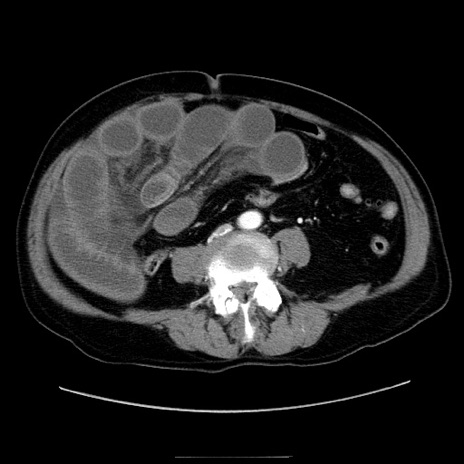

冠状断像

【症例】80歳代男性

【主訴】臍周囲痛

【現病歴】約6時間前から臍下部痛が出現。次第に腹部膨隆・背部痛も生じてきたため来院。背部痛の場所は変化しない。

【身体所見】意識清明、BT 36.3℃、BP  131/87mmHg、P 87bpm、SpO2 100%(RA)、臍周囲自発痛・圧痛あり、反跳痛なし、自発痛部位に一致して板状硬あり、腹部膨隆、腸雑音減弱、CVA tenderness両側陰性。

【データ】WBC 19600、CRP 0.33